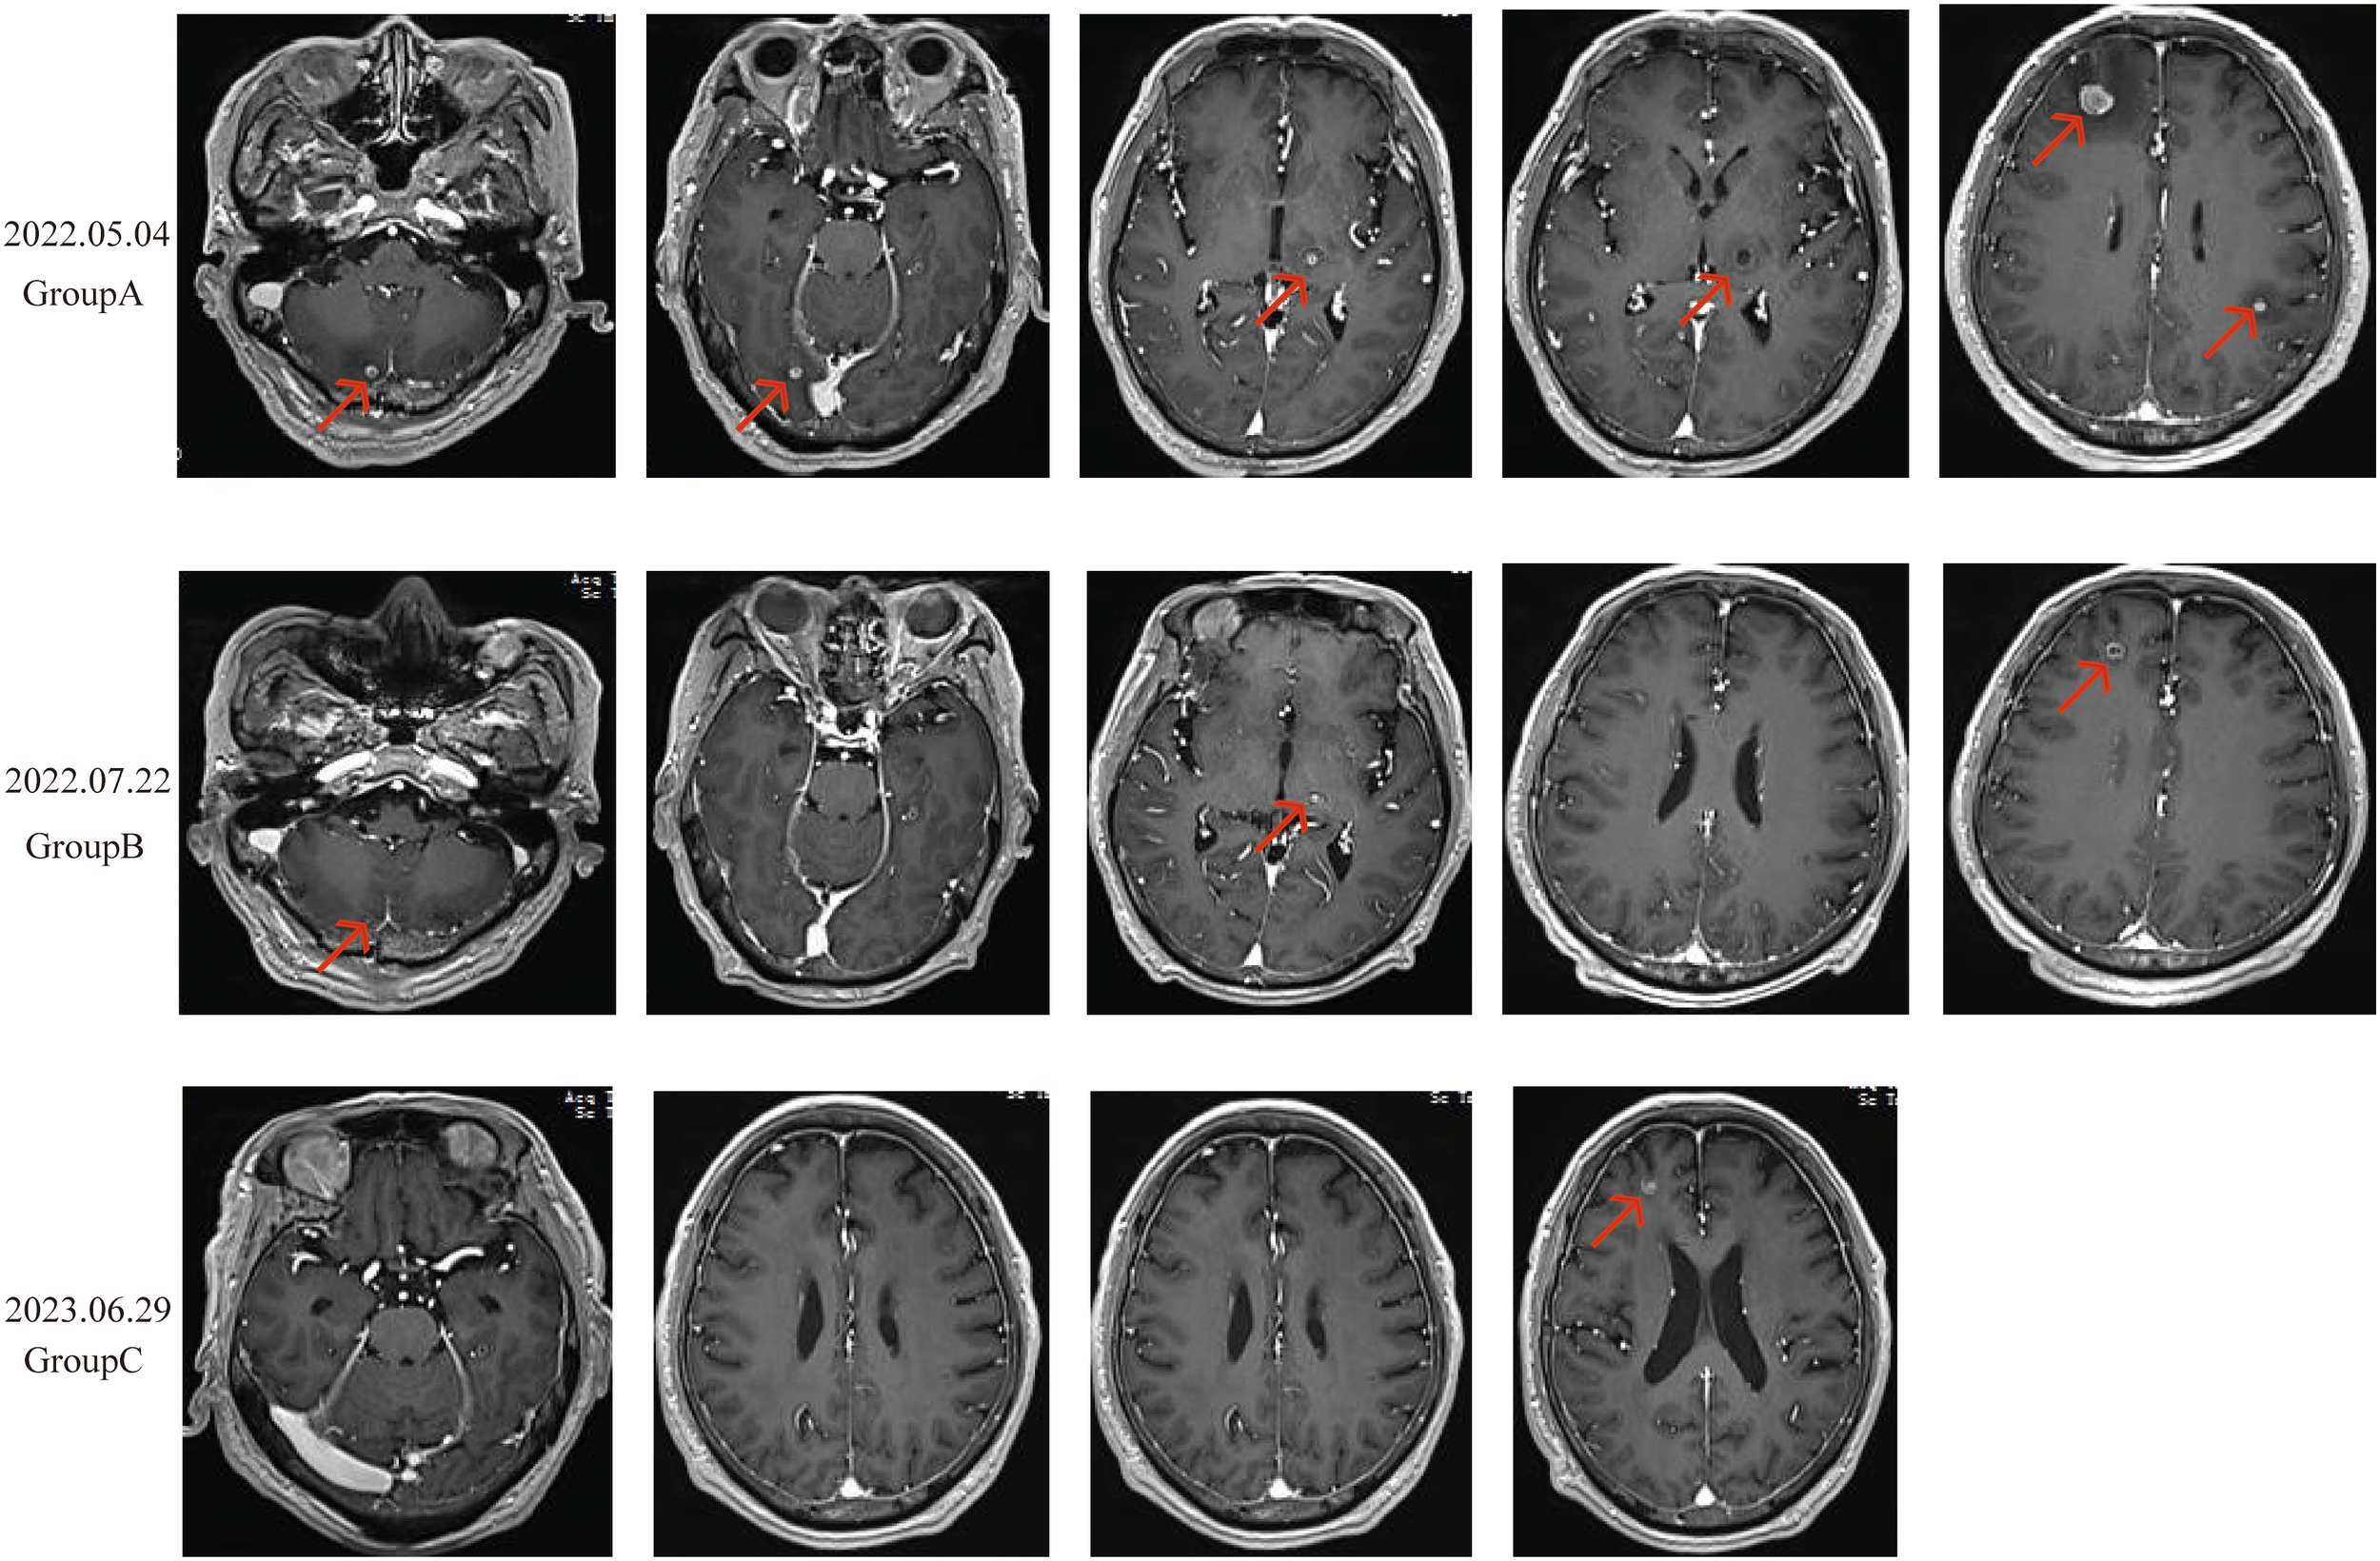

Enhanced brain MRI indicated abnormal signals in the right frontal-parietal lobes, left parietal lobe, left thalamus, and right cerebellar hemisphere, showing nodular and ring-like enhancement with clear boundaries. The largest lesion was located in the right frontal lobe, measuring approximately 11mm in its longest diameter, with surrounding patchy edema, suggestive of multiple metastases (Figure 3A). Bone scans revealed no bone metastases, and enhanced abdominal CT scans showed no signs of metastasis. Based on the comprehensive evaluation of clinical and examination results, the patient was diagnosed with stage IV PGCC (T4N2M1a according to the TNM staging system).

Due to the patient’s symptoms of headache and nausea, priority was given to whole-brain radiotherapy (WBRT) at a dose of 40Gy/23f and a local lesion dose of 50Gy/23f, over 23 sessions. High-throughput sequencing of lung tissue specimens was performed to evaluate genes associated with lung cancer, revealing a TP53 exon 4 c.313G mutation. PD-L1 expression (TPS) was 75%. Based on the guidelines from NMPA, NCCN, and ASCO, and a review of public databases, the patient was subsequently given Anlotinib at 12mg daily, administered for 2 weeks and 1-week off, constituting a 3-week (21 days) cycle. This was combined with Penpulimab injection at 200mg, administered every 3 weeks (21 days), as a first-line treatment regimen. Excitingly, after two cycles of combined treatment, a follow-up chest CT scan showed a significant reduction in the size of the tumor in the left upper lobe of the lung (30x32x34mm) and the mediastinal lymph nodes (Figure 1B). A follow-up enhanced brain MRI indicated that the abnormal signals in the right frontal-parietal lobe, left parietal lobe, left thalamus, and right cerebellar hemisphere appeared as spot-like and ring-like enhancements with clear boundaries. The brain metastases had significantly reduced in size, with the largest lesion in the right frontal lobe now measuring approximately 7mm in its longest diameter (Figure 3B). The patient’s clinical symptoms of brain metastases were remarkadly relieved, and the quality of life improved significantly.

Figure 3

Radiological changes in brain metastases before and after treatment. (A): Nodular and ring-enhanced abnormal signals in the right frontal-parietal lobe, left parietal lobe, left thalamus, and right cerebellar hemisphere. Multiple metastases are observed, with the largest lesion in the right frontal lobe, measuring approximately 11 mm in length, surrounded by small patches of edema. (B): The brain metastases in the same locations showed significant shrinkage, with most lesions showing reduced enhancement. The largest lesion in the right frontal lobe measured approximately 7 mm in length. (C): The metastases in the left parietal lobe, left thalamus, and right cerebellar hemisphere disappeared. The largest lesion, located in the right frontal lobe, measured approximately 7 mm in length.

Two months later, a follow-up examination showed that the tumor had shrunk to 21x29x22mm, and the mediastinal lymph nodes had also significantly reduced in size (Figure 1C). Subsequent bi-monthly chest CT scans showed continued tumor shrinkage. By November 18, 2022, a follow-up chest CT scan showed that the tumor had significantly reduced to 12x19x17mm, with no significant enlargement of the mediastinal lymph nodes (Figure 1D). Follow-up enhanced brain MRI indicated that the metastases in the left parietal lobe, left thalamus, and right cerebellar hemisphere had disappeared, with the largest lesion in the right frontal lobe remaining at approximately 7mm (Figure 3C). According to the RECIST 1.1 criteria, the patient’s condition was classified as partial response (PR).